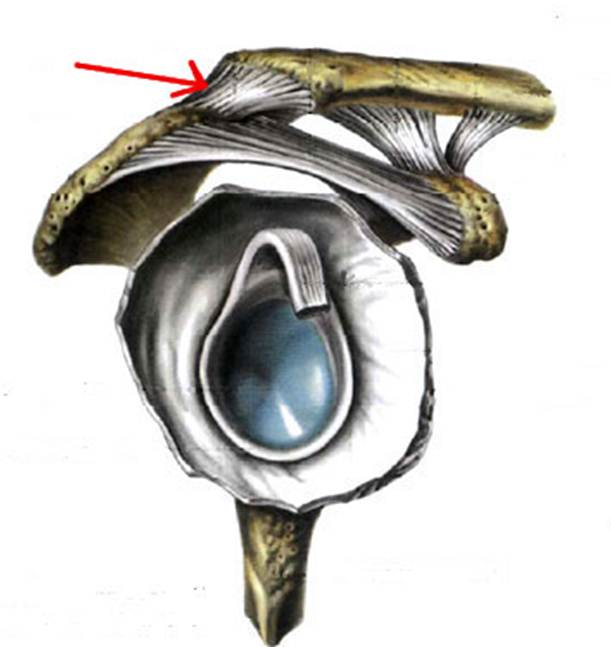

S: Стрелка указывает на art. humeri (латинский язык).

S: Стрелка указывает на tendo m bicipitis brachii

S: Стрелка указывает на lig. coracoacromiale

S: Цифрой 6 обозначена суставная капсула плечевого сустава (русский язык).